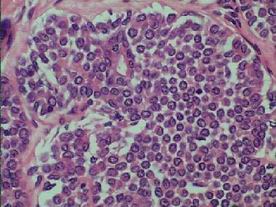

DCIS classified not in LCIS

nuclear grade (low, intermediate, high)

architecture predominant

comedo, cribriform, papillary

micropapillary, solid, spindle, streaming...

presence /type of necrosis